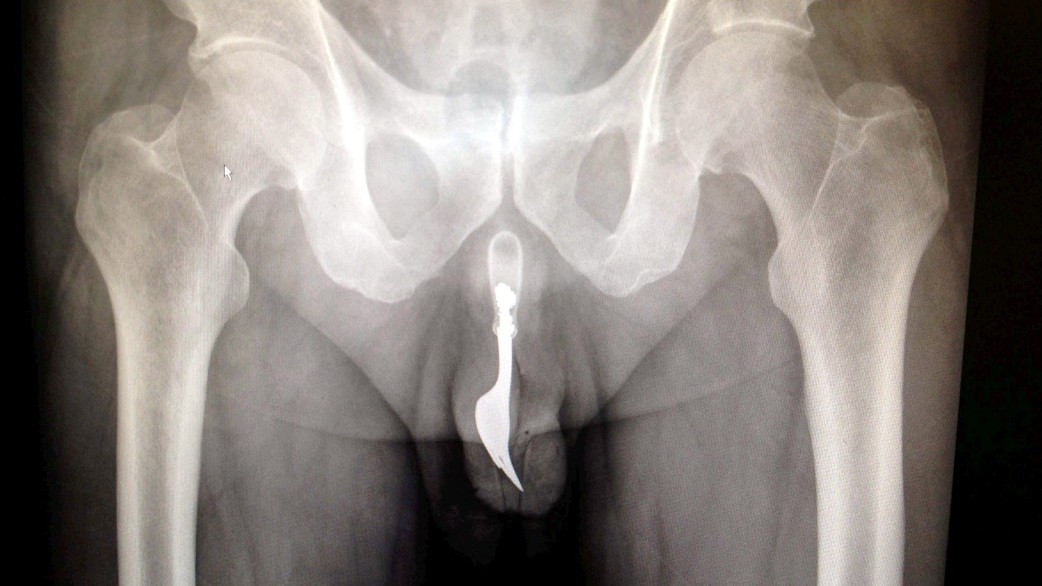

FOTO. Dôchodcovi našli v penise 10-centimetrovú vidličku!

CANBERRA / Keď lekári prijali na pohotovosti v Austrálii staršieho pacienta, ktorý sa sťažoval na krvácanie z pohlavného orgánu, to ešte netušili, čo mu v ňom nájdu. Rontgenová snímka ich musela šokovať! V penise mal totiž strčenú 10 cm dlhú, oceľovú kuchynskú vidličku! A pravda o tom, ako sa mu tam dostala, nenechala na seba dlho čakať...

Lekári z austrálskej Canberry sa rozhodli zverejniť jeden z kontroverzných prípadov, kedy z pacientovho tela museli chirurgicky odstraňovať cudzí objekt. Nielen z tela, ale rovno z jeho pohlavného orgánu! Išlo pritom o 70-ročného muža, ktorý sa napokon ku všetkému priznal.

Podľa lekárskej správy, ktorú zverejnil denník The Daily Mail, sa muž chcel sexuálne uspokojiť, no jeho sexuálne dobrodružstvo vypálilo horšie, než čakal. Vidlička mu totiž ostala strčená v tele a spôsobila obrovské bolesti. Aj napriek nim sa však zahanbený dôchodca odvážil lekársku pomoc vyhľadať až o 12 hodín! Lekári muža napokon uspali a vidličku odstránili aj za použitia lubrikantu a pinzety... Procedúra bola úspešná a krátko po operácii mohol muž opustiť bez vážnych následkov nemocnicu.